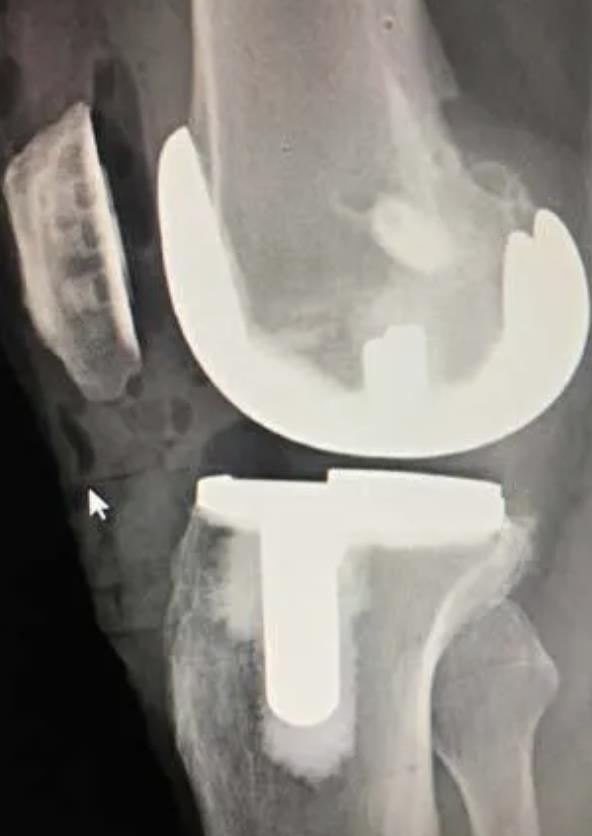

[Blocked from Release] iTotal Identity

https://upload.orthobullets.com/topic/423283/images/01f9c561-10a6-4863-9b50-fc5308e5afb5_screenshot_2025-09-17_at_4.42.53_pm.jpg

• The iTotal Identity sets a new standard in knee replacement technology

• Patient-specific implants are designed around individual anatomy to promote physiologic kinematics, stability, and long-term joint health

• By leveraging advanced imaging technology and a proprietary database, iTotal Identity ensures that each implant is uniquely crafted to match the patient’s individual anatomy

• The platform personalizes implant geometry and streamlines intraoperative steps to support precise placement and efficient workflows